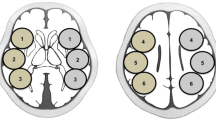

Using the SEE-JET program, CBF was automatically measured at rest and after acetazolamide challenge, and ROIs were automatically set for the territories of the anterior cerebral artery (ACA), middle cerebral artery (MCA), and posterior cerebral artery (PCA) in the brain surface of each hemisphere (Fig. 1A, B) [17]. We measured preoperative rCBF and CVR and postoperative rCBF in the ipsilateral MCA territory. The quantitative CBF change was then calculated as follows: quantitative CBF change (%) = 100 × [(postoperative rCBF − preoperative rCBF)/preoperative rCBF]. In this study, HP was defined as the upper value of the 95% CI of the immediate quantitative CBF change. If HP was detected, rCBF was also measured on PODs 3 and 7.

ROI placement for measuring CBF using the SEE-JET program (A, B) and NEURO FLEXER (C, D). SEE-JET automatically measures CBF in territories of the anterior cerebral artery (light blue), middle cerebral artery (orange), and posterior cerebral artery (yellow) in the brain surface of each hemisphere. NEURO FLEXER automatically sets ROIs in the territories of the middle cerebral artery (C) and cerebellum (D) in the brain parenchyma of each hemisphere

Using the NEURO FLEXER program, CBF was automatically measured and ROIs were set automatically for the territories of the ACA, MCA, PCA, basal ganglia, thalamus, pons, vermis, and cerebellum (Fig. 1C, D). Using rCBF measured automatically in the ROI of the ipsilateral MCA and cerebellum regions in the brain parenchyma, the qualitative CBF ratio (MCA/cerebellum ratio) was calculated as follows: qualitative CBF ratio (%) = 100 × (rCBF in ipsilateral MCA territory/rCBF in ipsilateral cerebellum). The qualitative CBF change was then calculated as follows: postoperative qualitative CBF ratio − postoperative qualitative CBF ratio [18].